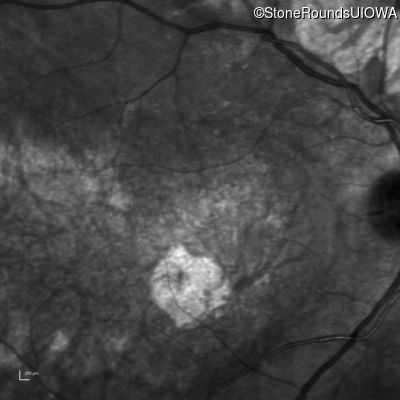

Infrared Fundus Photograph - Left - 20/80

Exemplar